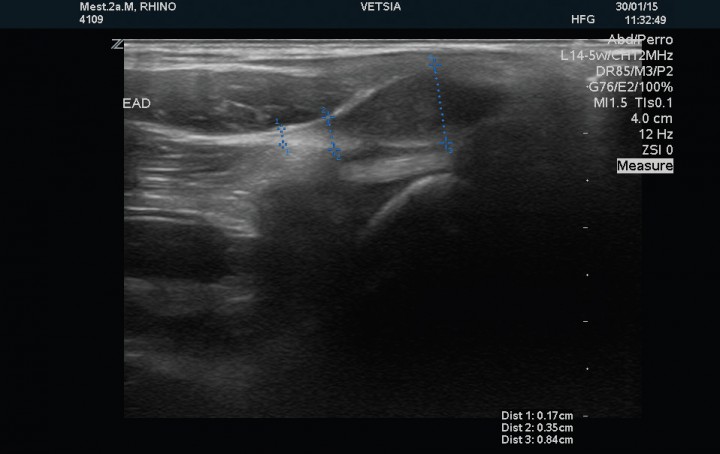

Se realizó examen ecográfico de ambas articulaciones escápulo-humerales con sonda lineal de 12 MHz; los hallazgos ecográficos observados en la articulación izquierda mostraron un tendón del músculo infraespinoso de estructura normal y 2,8 mm de grosor en corte transversal, el tendón del músculo supraespinoso presenta un grosor de 1,7 mm en su porción tendinosa, 4,2 mm en la transición fribrocartilaginosa y de 7,2 mm en la porción fibrocartilaginosa próxima al tubérculo mayor del húmero (zona de máximo grosor), evidenciándose en esta región, próxima a la superficie perióstica, una estructura ecogénica que producía una sombra acústica distal de 3,7mm de diámetro compatible con un foco de mineralización intratendinosa (Fig. 2). El tendón del músculo bíceps braquial presenta su inserción normal en la tuberosidad supraglenoidea con un grosor de 2,7 mm, mostrando su cápsula sinovial un engrosamiento en su porción más proximal (Fig. 3). La cabeza humeral y el cartílago articular se evidencian de contorno liso y grosor normal. La articulación escapulo-humeral derecha no presentaba ningúna alteracion (Fig. 4). La imagen ecográfica es compatible con tendinopatía del tendón del músculo supraespinoso, con mineralización en fibrocartílago de 3,7 mm y signos leves de sinovitis del bicipital.

<p>Corte sagital del tendón del músculo supraespinoso izquierdo en el que se muestra la mineralización (entre los cursores) como una superficie ecogénica irregular con sombra acústica posterior.</p>

Figura 2

Corte sagital del tendón del músculo supraespinoso izquierdo en el que se muestra la mineralización (entre los cursores) como una superficie ecogénica irregular con sombra acústica posterior.